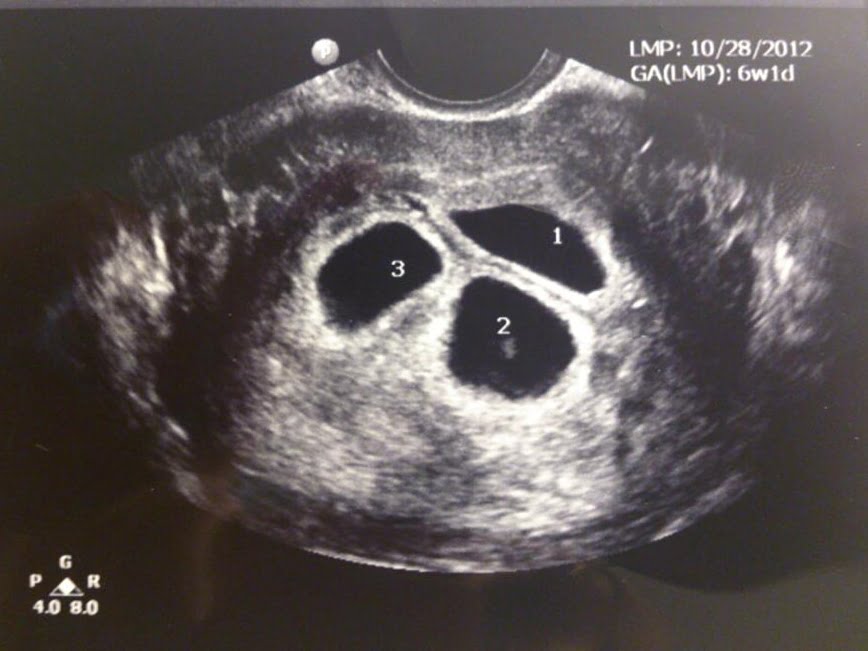

Fetal Redüksiyon Kıbrıs Doğuş Tüp Bebek Merkezi From Pinterest

Fetal Redüksiyon Kıbrıs Doğuş Tüp Bebek Merkezi